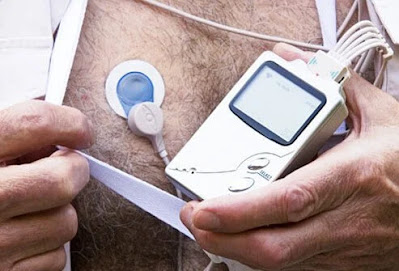

Έλεγχος καρδιακών παθήσεων: Holter Monitor

Μια οθόνη Holter φοριέται συνεχώς για 1 έως 2 ημέρες για να καταγράψει τη δραστηριότητα της καρδιάς.

Πολλοί άνθρωποι έχουν διαλείπουσα συμπτώματα, όπως διαλείποντα πόνο στο στήθος ή περιστασιακά συναισθήματα της καρδιάς τους να χτυπάει γρηγορότερα ή ακανόνιστα. Ωστόσο, το ΗΚΓ τους δεν εμφανίζει αλλαγές. Για να ανιχνεύσει αυτές τις διαλείπουσες αλλαγές, μια συσκευή που ονομάζεται οθόνη Holter μπορεί να φορεθεί για αρκετές ημέρες για να καταγράψει την ηλεκτρική λειτουργία των καρδιών.

Μια οθόνη Holter είναι παρόμοια με ένα τεστ αντοχής, αλλά φοριέται για 1 ή 2 ημέρες και παρέχει μια συνεχή καταγραφή που μοιάζει με ΗΚΓ της ηλεκτρικής δραστηριότητας της καρδιάς κατά τη διάρκεια αυτών των ημερών.

Οι περισσότεροι γιατροί θα ζητήσουν από τον ασθενή να τηρεί ημερολόγιο για την ώρα που κάνει συγκεκριμένες δραστηριότητες (για παράδειγμα, περπατώντας ένα μίλι ξεκινώντας από τις 7:20 π.μ. και τελειώνοντας στις 7:40 π.μ.) και να απαριθμεί τυχόν συμπτώματα (για παράδειγμα, “βίωσε λαχάνιασμα ή γρήγορους ακανόνιστους καρδιακούς παλμοίύς στις 7:35 π.μ. »). Οι εγγραφές της οθόνης Holter μπορούν στη συνέχεια να εξεταστούν με βάση το πότε εμφανίστηκαν ορισμένα συμπτώματα.